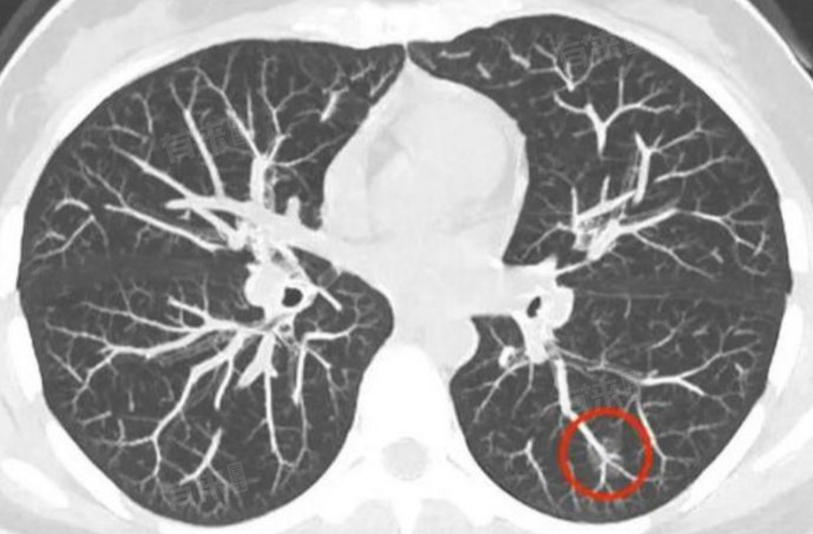

- 若肺部钙化结节直径超过6mm,特别是当结节周围有磨玻璃样改变时,或结节增长速度较快,患者出现明显不适症状,可能需要考虑手术治疗。